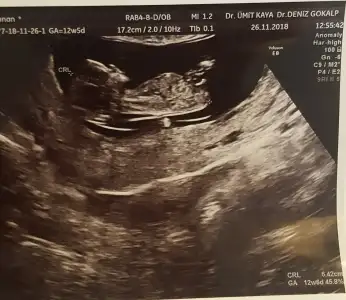

Ne dediler peki,kemik yapısından da çok net bulunabiliyorlar

İlk doktor 11+4 te açı bulamamış kızı andırıyor demişti. Bugün başka doktora gittim 12+5 ti erkek dedi çıkıntı var ama erken daha dedi bilmiyorum yani farklı dediler

Bana nub tahmini yok mu :)